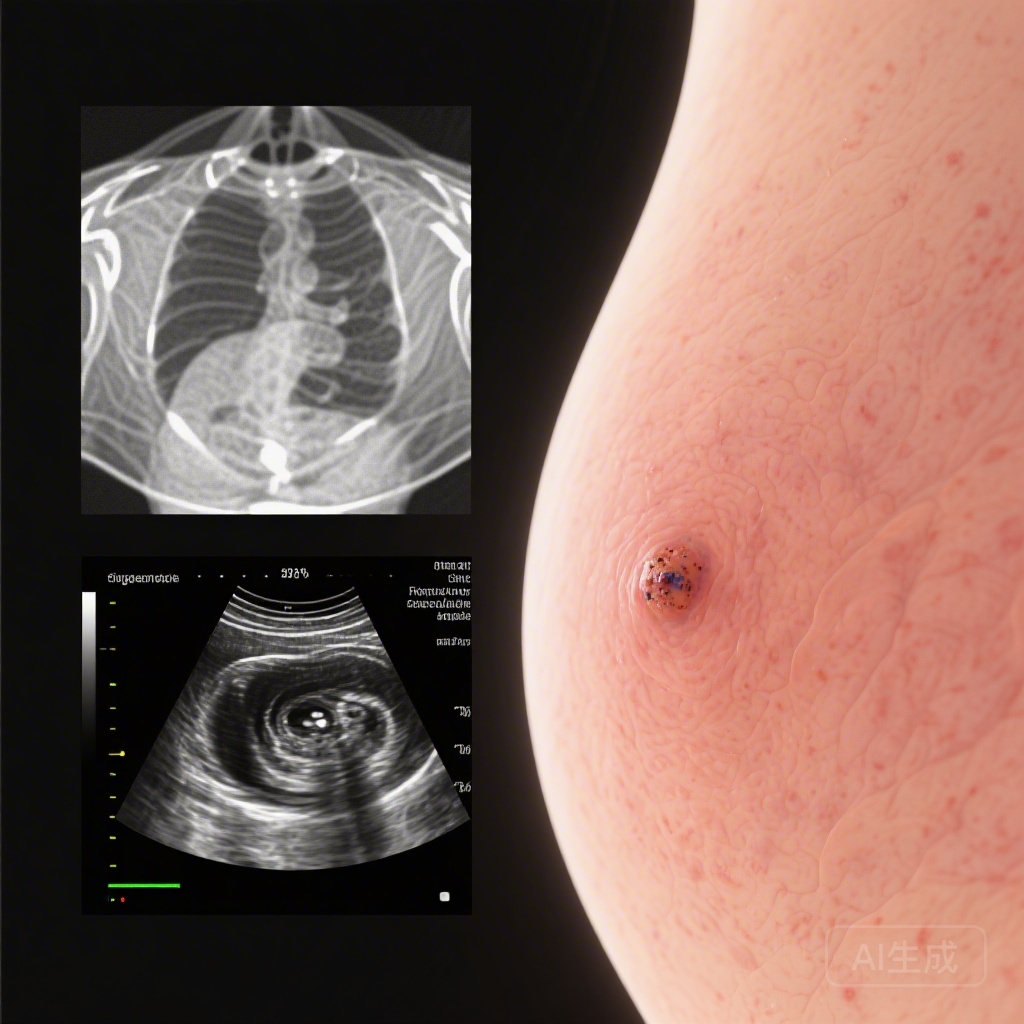

In many Asian countries, the peak incidence of breast cancer occurs among women in their 40s, a demographic that often presents with dense breast tissue. Traditional mammography (MG) screening faces significant limitations in this population; the high density of fibroglandular tissue can mask malignant lesions, leading to a higher rate of false negatives. To address this diagnostic gap, the Japan Strategic Anti-cancer Randomised Trial (J-START) was initiated to evaluate whether adjunctive ultrasonography (US) could improve screening outcomes. While initial reports confirmed that the addition of US significantly increased the detection rate and sensitivity of screening, the long-term impact on advanced cancer incidence remained a critical unanswered question until now.

For clinicians and health policy experts, the results of this secondary analysis provide the necessary evidence to support a shift in screening paradigms. The masking effect of dense breasts is a well-documented phenomenon; by using sound waves rather than X-rays, ultrasonography can identify masses that are isodense with surrounding tissue.